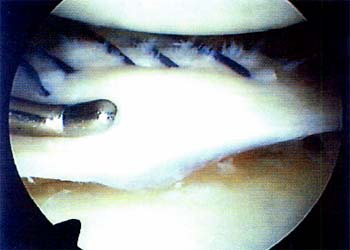

Nuestras indicaciones se extendieron a lesiones verticales longitudinales del tercio periférico (zona roja) y lesiones menisco capsulares. (Foto 1). Coincidimos con Weiss y col. en no suturar las lesiones que afectan sólo una superficie del menisco o lesiones parciales y aquellas menores a un centímetro sin desplazamiento central, a las cuales realizarnos abración de los bordes, o dejamos evolucionar. Basados en los trabajos de irrigación de Arnoczky (1) no suturamos el borde periférico adyacente al ojal del poplíteo por ser esta región escencialmente avascular.

03_01_02_Foto1

Foto 1: Ejemplo de Lesióm vertical longitudinal en zona   Foto 3: Puntos en "U" en el plano vertical dados con rosa.   hilo reabsorvible (Vcril Ng 1)